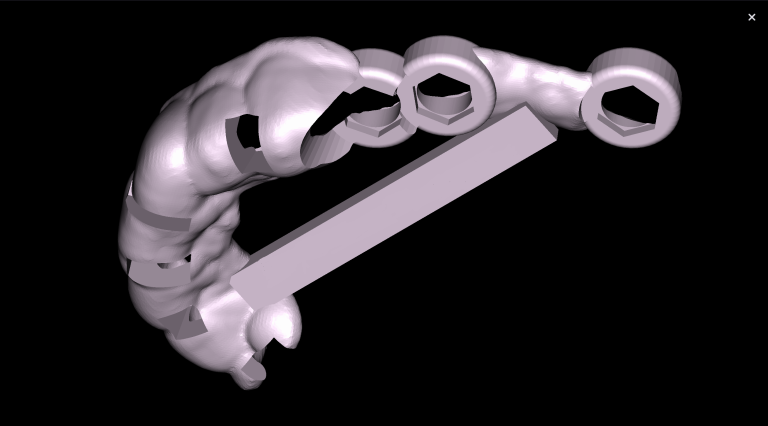

Objective: To reduce the amount of time taken to create a treatment plan for eliners. Problem: When planning tooth movements, the orthodontist needs a significant amount of time to evaluate the clinical case and perform calculations to achieve the most functional and accurate final tooth position.

Solution: Diagnocat’s reports, based on CBCT and intraoral scans (STL files), help the clinician to quickly and accurately make decisions about treatment tactics and final tooth position, and to plan comprehensive treatment according to the individual needs of the patient